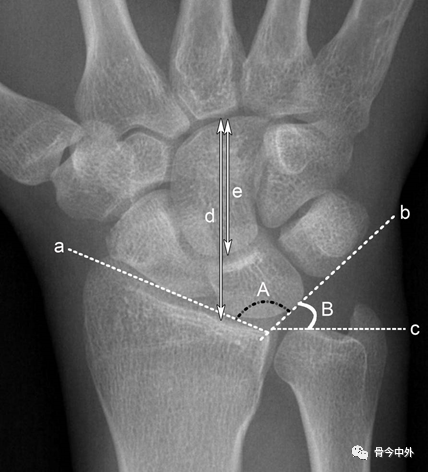

图4 a.桡骨纵轴线;b.桡骨纵轴线垂线;c.桡骨远端关节面切线;d.尺骨远端关节面水平线。A.桡骨内倾角;B.桡骨茎突长度;C.尺骨茎突长度 。

A.正常为15~35˚ 。若此角度改变,提示桡骨远端骨折或腕关节脱位。

B.正常为8~18mm,且桡骨茎突较尺骨茎突低1~1.5cm。若此长度改变,提示桡骨远端骨折。C.正常为2~8mm。若此长度改变,提示尺骨茎突骨折或尺骨茎突过长(尺骨茎突撞击综合症)